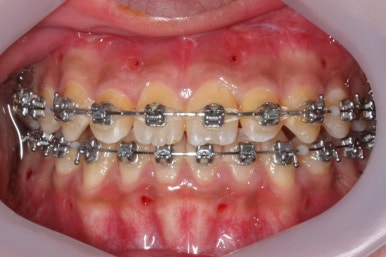

부산주걱턱교정 키다리아저씨치과에서 장치를 부착하였습니다.

이번에 사용된 장치는 자가결찰 메탈이며 가장 부피도 작고 튼튼하고 여러 장점이 있습니다.

점점 수술전 교정이 진행되는 모습입니다.

각각의 위턱과 아래턱뼈 제위치에 맞게 윗니는 뒤로, 아랫니는 앞으로 내어주게 됩니다. 수술직전까지는 어떻게 보면 교합은 점점 나빠진다고 볼 수 있씁니다.

이 과정에서 힘들어 하시는 분들이 많으신데요. 점점 교합이 서로 멀어질수록 수술은 예쁘게 잘 된답니다.